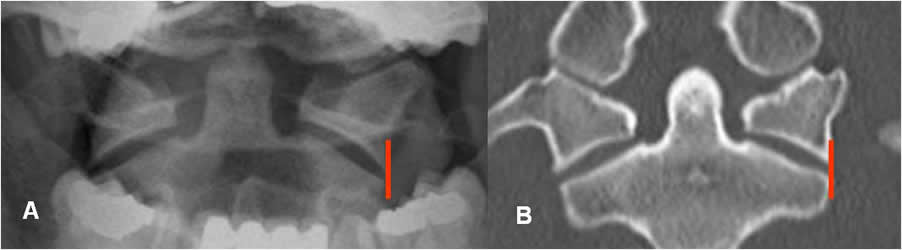

En la proyección de odontoides las masas laterales del atlas y axis, deben estar alineadas. (Fig 5). Hasta 3 mm de desplazamiento lateral bilateral, puede ser normal en los niños y 2 mm en los adultos. (6). (Fig 6).

Fig 5. Odontoides normal.

A: Rx AP y B: TAC reconstrucción coronal. Odontoides normal, con alineación de las masas laterales de C1 y C2.